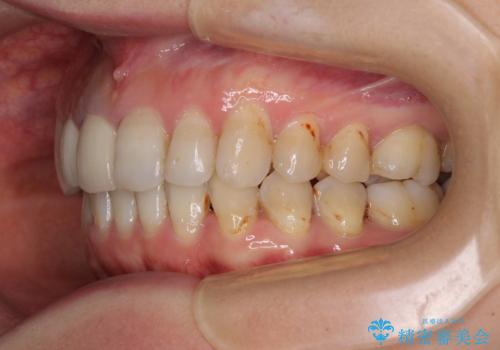

- 前歯の歯並びやむし歯治療の跡、奥歯の銀歯を気にして来院された患者様です。

インビザラインによる矯正治療の後に虫歯や銀歯をセラミックにて補綴することとしました。

前歯のむし歯治療の跡や奥歯の目立つ銀歯がなくなり、明るい口元になりました。